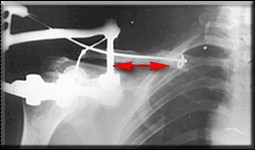

Если заинтересует вариант фиксации трансплантата, представленный в приложении, с удовольствием поделимся опытом.